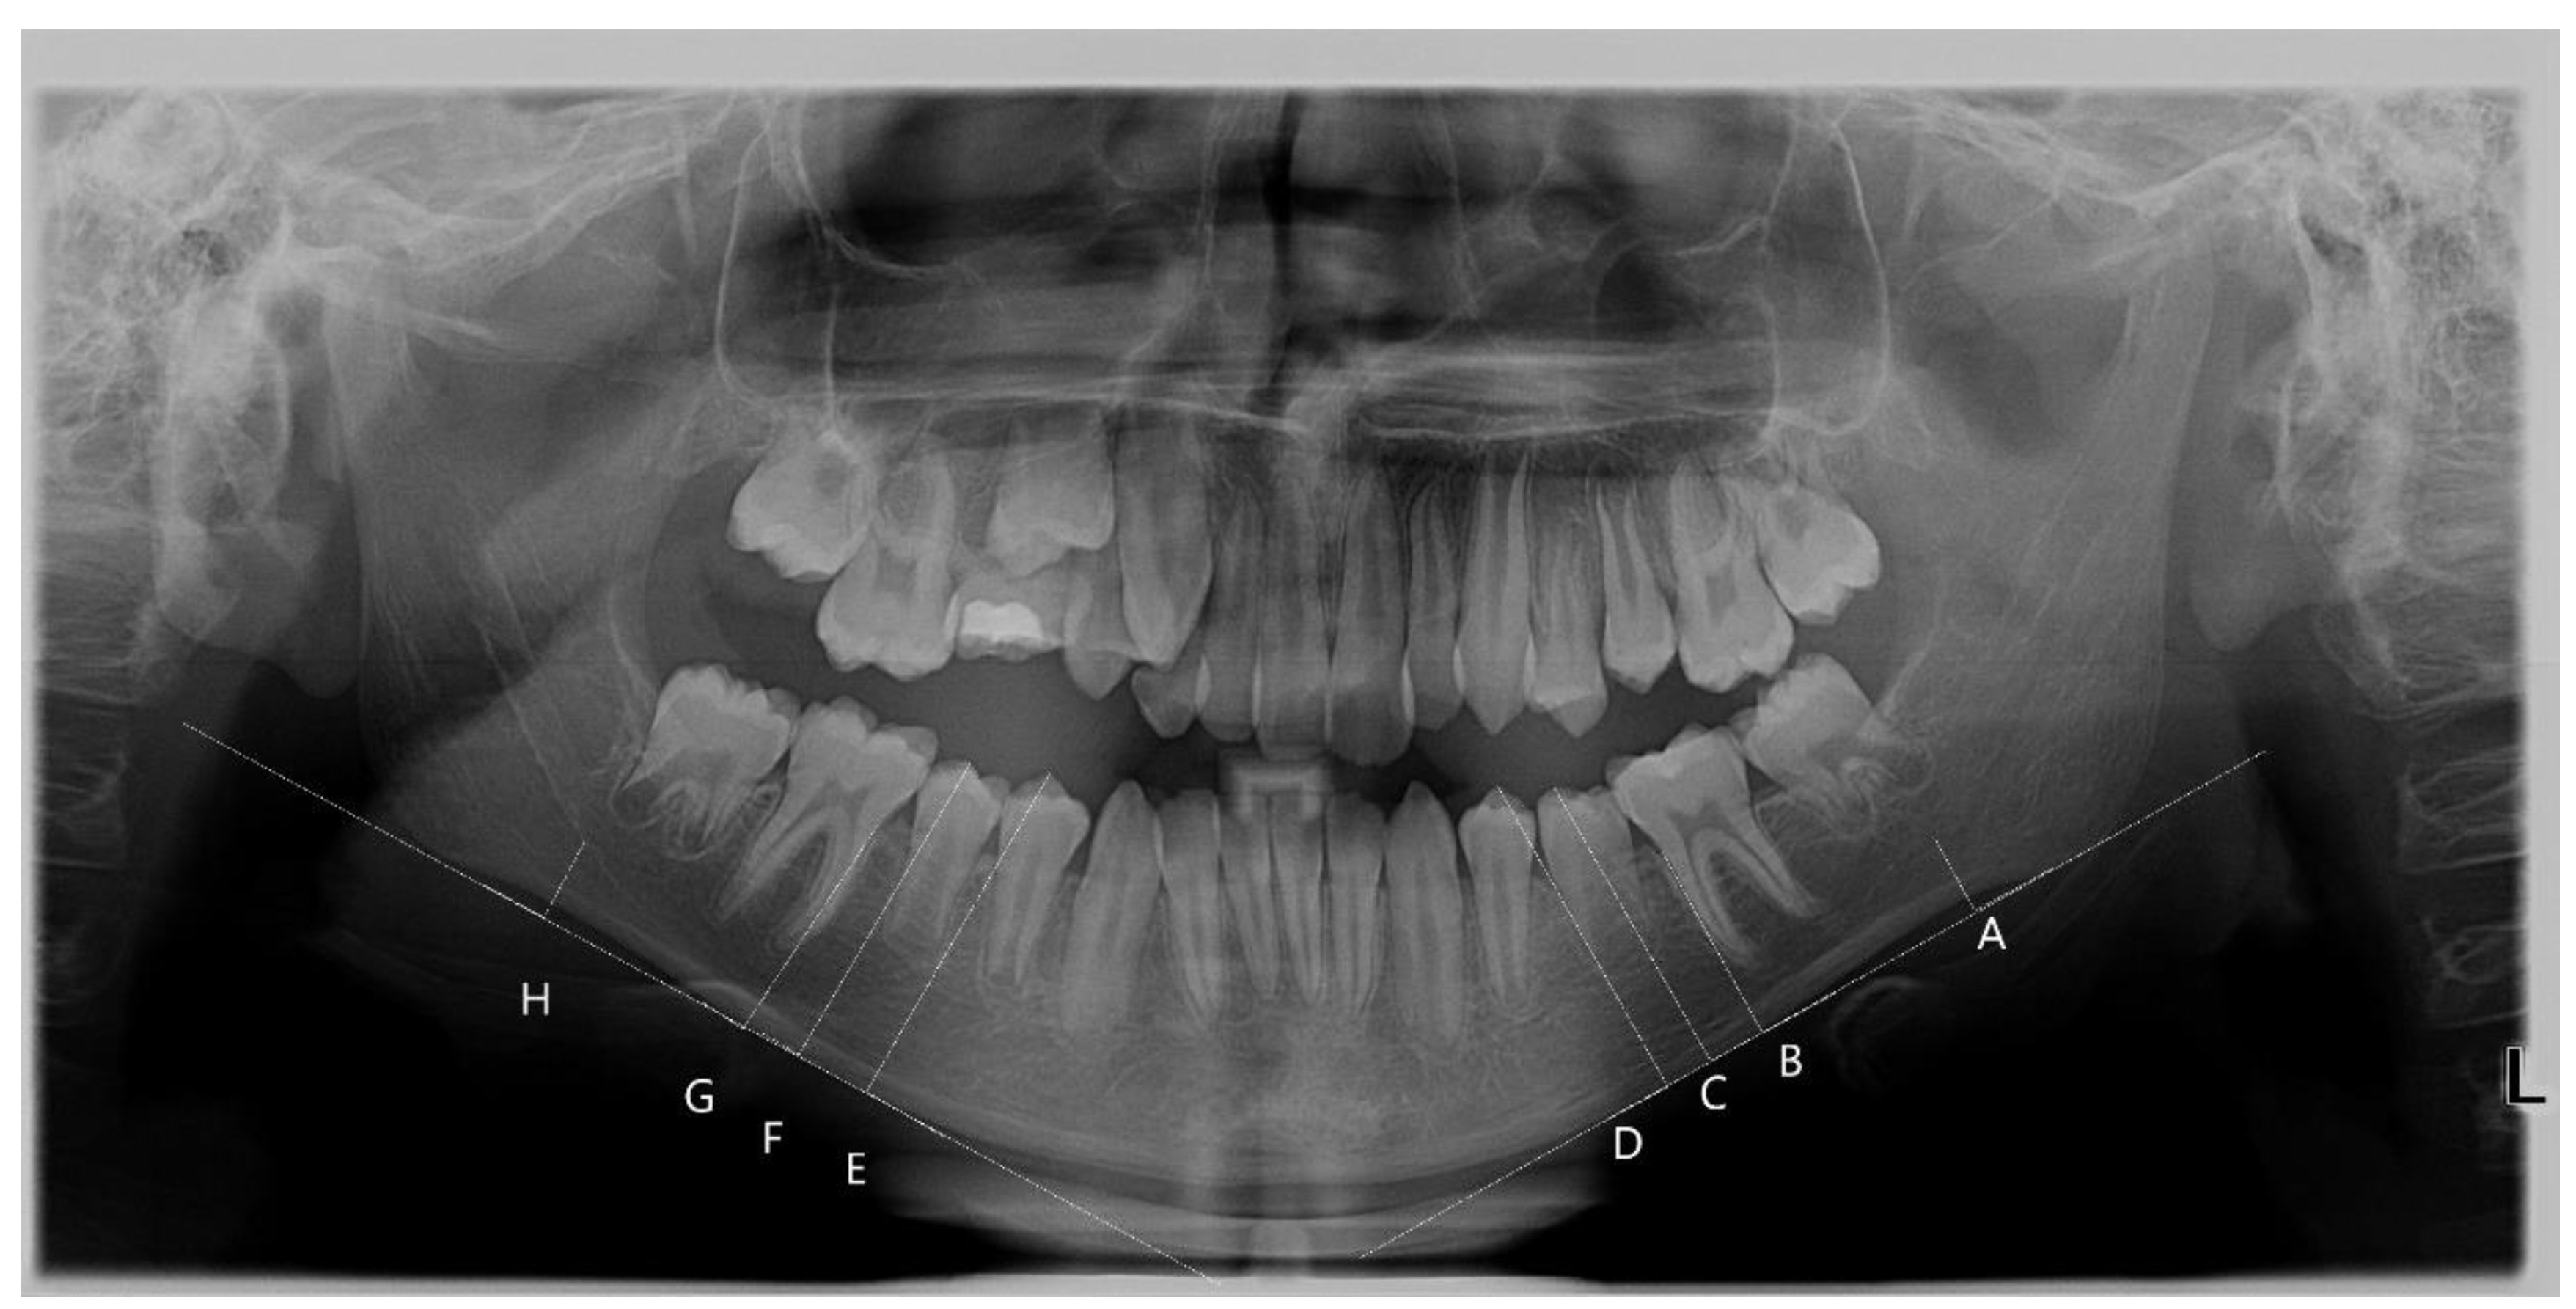

2.5. Quantitative Bone Assessment (Mandibular Cortical Width, MCW)

- Antegonion—the deepest point of the antegonial notch concavity (A, H);

- The mesial cementoenamel junction of the first molar perpendicular to the mandibular base (B, G);

- The most superior cusp tip of the second premolar perpendicular to the mandibular base (C, F);

- The most superior cusp tip of the first premolar perpendicular to the mandibular base (D, E).